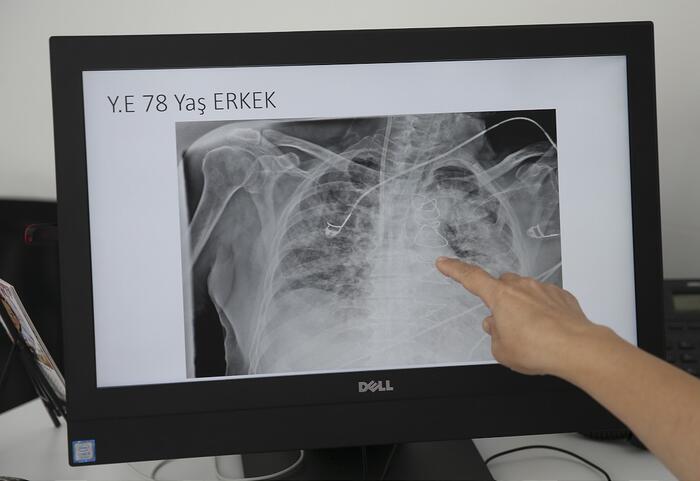

Anadolu Ajansı (AA) Ankara Şehir Hastanesinde Kovid-19 tedavisi gören hastalara ait akciğer görüntülerine ulaştı. Görüntülerde, hastalığın ne kadar hızlı ilerlediği ve akciğerleri nasıl tuttuğu ortaya çıktı.

Ankara Şehir Hastanesi Göğüs Hastalıkları Kliniği İdari ve Eğitim Sorumlusu Prof. Dr. Ayşegül Karalezli, AA muhabirine yaptığı açıklamada, salgının son hızıyla devam ettiğini belirterek, "Mart, nisan, mayıs ayında gördüğümüzden daha şiddetli ve daha hızlı sanki, çember daha çok daraldı. Etrafımızda bize yakın insanların kovid pozitif ve akciğer tutulumu ile geldiğini görüyoruz." ifadesini kullandı.

Prof. Dr. Karalezli, koronavirüsün akciğerleri etkilediği durumda, nefes almanın çok zor olduğunun altını çizerek, halen hastaneye başvuranların da son derece ciddi akciğer tutulumlarının olduğuna vurgu yaptı.

Normalde insanların oksijen seviyelerinin yüzde 98 olduğunu ifade eden Karalezli, koronavirüse yakalananlarda oksijen seviyenin yüzde 70'lere kadar düştüğünü belirtti. Bu durumdaki hastaların oksijen seviyelerini değişik makinalar ve yüksek akım oksijen cihazlarıyla düzeltmeye çalıştıklarını anlatan Karalezli, diğer zatürre durumlarında bu kadar ciddi oksijen düşüklüğü görülmediğine işaret etti.

"İnsanların çok dikkat etmesini istiyoruz. Akciğere girdi mi bunun çıkışı kolay olmuyor. Altta yatan hastalığı varsa biraz ileri yaştaysa çok riskli. Şu an bizim takip ettiğimiz hasta yaş aralığı 40-60 yaş arası. Gençlerde hastalığın seyri çok hızlı gidiyor. Koronavirüs tüm organları tutabiliyor. Akciğer tutulumu varsa tablo kaçınılmaz olarak ilerliyor. İnsanların son derece duyarlı olmasını istiyoruz. Bizler çok yorulduk. Kovid hastalarıyla uğraşıyoruz bakmamız gereken diğer hastalarımız da var. Onlar da sürekli randevu almaya çalışıyorlar."